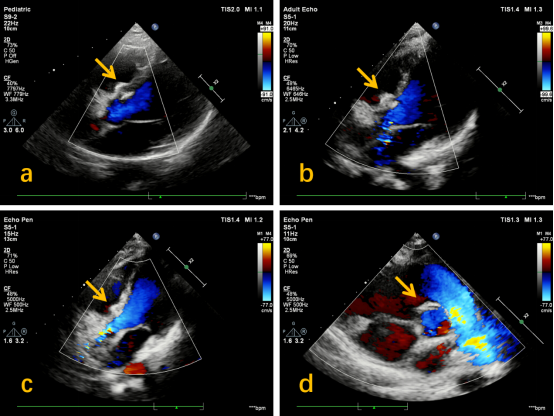

图2:手术后复查心脏彩超结果(a:术后1个月;b:术后3个月;c、d:术后1年。箭头所示为封堵器形态,如图所见,在术后1年显示封堵器已吸收,超声显示缺损已完全闭合,与正常室间隔无差异)